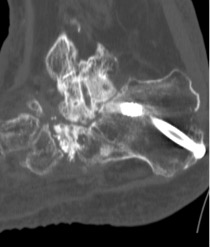

DUAL-ENERGY CT (DECT)

DECT demonstrates diffuse urate deposits in gouty arthritis (green areas)

Corresponding CT shows diffuse chondrocalcinosis

Generation of dual-energy CT image

CT technique that uses two separate x-ray photon energy spectra, allowing differentiation of tissues based on their attenuation properties at different energies.

Indications

Crystal arthropathies (gout, CPPD) – diagnosis confirmation/exclusion in subclinical disease, atypical presentations or gout-mimickers, problem-solving, monitoring treatment response by measuring disease burden.